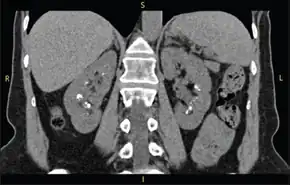

Classically, MSK is seen as hyperechoic papillae with clusters of small stones on ultrasound examination of the kidney or with an abdominal x-ray. The irregular (ectatic) collecting ducts are often seen in MSK, which are sometimes described as having a "paintbrush-like" appearance, are best seen on intravenous urography. However, IV urography has been largely replaced by contrast-enhanced, high-resolution helical CT with digital reconstruction.[9]